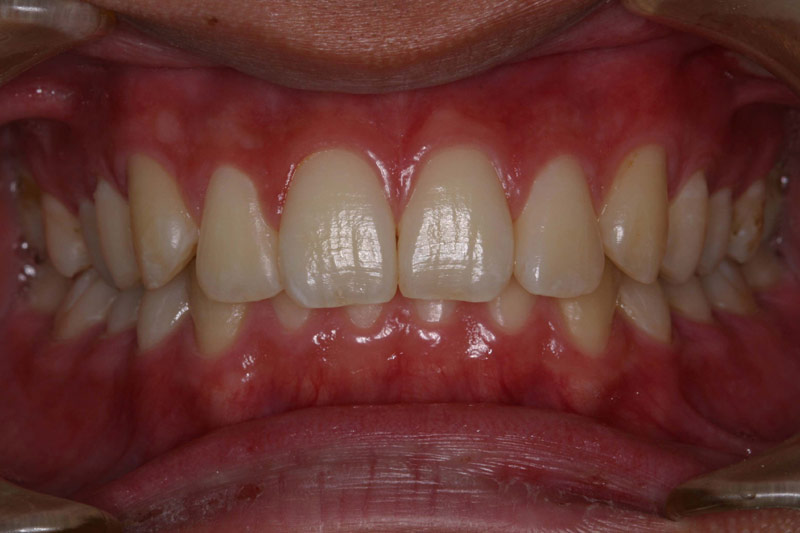

定期健診を継続し、虫歯に一回もなったことのない歯並びのきれいな患者さんが多く育っています。

子供達を健康で綺麗な歯並びの永久歯列に誘導していくことを咬合育成と言います。開業時から来院していた子供達を見ていて、どうしたら綺麗な歯並びにできるのかを研究してきました。最近その成果が上がるようになり多くの子供達が健康できれいな歯並びをもった大人になって来院するようになっています。対外的にも「講演・論文」のページにあるように各地の歯科大学や歯科医師会からその分野の講演を依頼されるようになり、いつのまにか須貝歯科医院の得意分野になってしまいました。永久歯への生え替わりの時期が最も重要な時期です。簡単な装置で歯並びを改善していくのですが患者さんによっては矯正専門医に紹介しなければならないケースもあります。その時は地元の信頼できる矯正専門医をご紹介しています。

上の前歯は下の前歯より前にないといけませんが、前歯の生え替わりの時に1本逆に生えてきました。そのままではきれいな歯並びにはなりそうもありません。この時が治療のタイミングです。簡単な矯正装置で改善しただけでその後きれいな永久歯列になりました。